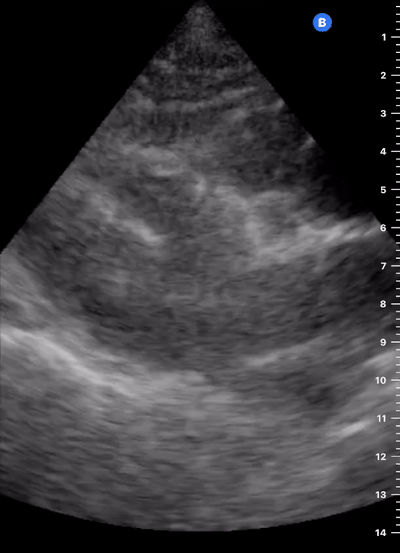

IVC exploration is best from the subxiphoid approach with longitudinal and transverse images. The IVC should be assessed in terms of overall size and collapsibility. The diameter is typically measured at its largest (end of expiration) at 1-2 cm distal to where the hepatic veins join the vena cava. An IVC diameter of ≥ 2 cm, especially with minimal or no collapsibility, is considered plethoric and correlates with increased RA pressure. An IVC of < 1 cm, particularly with complete collapse, is considered flat and indicates low preload and potential fluid responsiveness. An IVC diameter between 1 and 2 cm is typically normal.